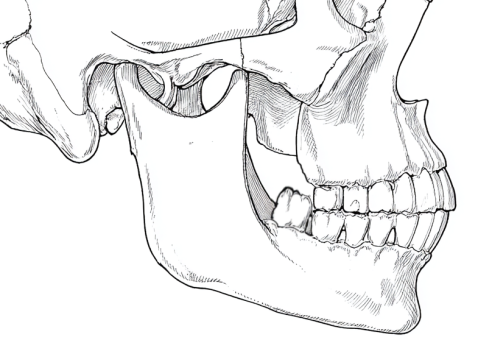

親知らずは、一番最後に生えてくるため、現代人のあごの中では生える場所が残されていません。骨の中に埋まったまま出てこなかったり、横や斜めに生えてきたりして、今日では完全な形で生えてくる人は稀です。

4.顎が小さくて、生える場所が無いので、変な場所に生えたり、骨の中に潜って頭を出さず炎症を起こします